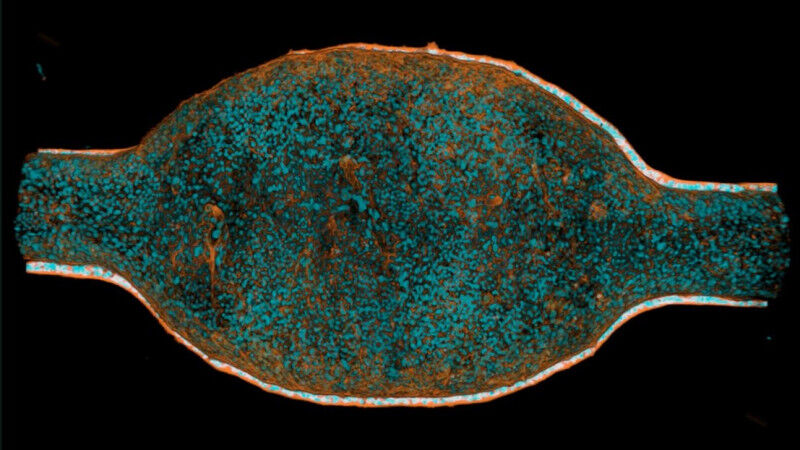

A promising new drug for an invasive type of breast cancer

Researchers have developed preclinical models for invasive lobular carcinoma and trialed a new drug. It slows tumor growth effectively by targeting specific features of the disease and opening the door to future clinical trials.

A human mini-bladder shows the culprit of recurrent infections

Researchers at EPFL, Heidelberg University and Roche have built a human mini-bladder to show how urine composition weakens bladder tissue, helping infections recur even after antibiotics.